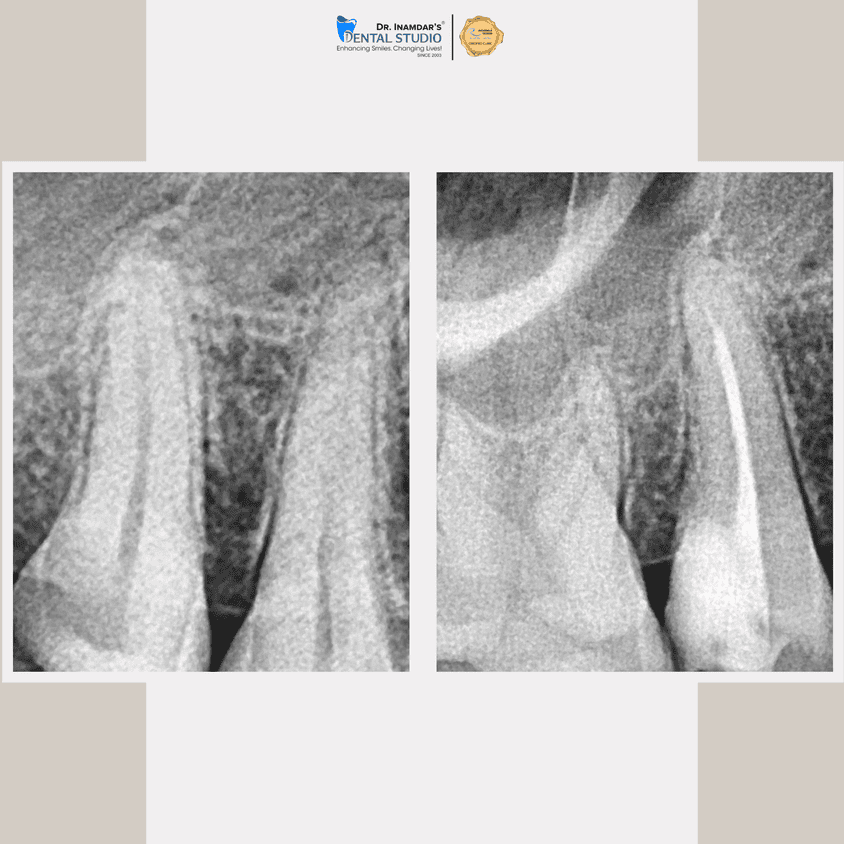

We begin with a detailed dental examination and digital X-rays to identify the source of infection.

The infected tissue is gently removed, and the tooth is thoroughly cleaned and disinfected.

The tooth is sealed and usually protected with a crown to restore strength and function.